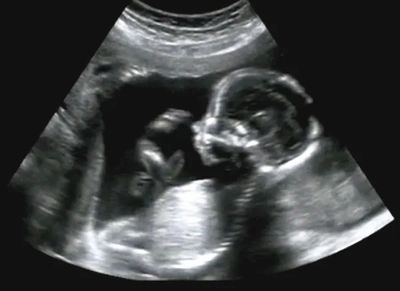

In the state of New Jersey, minors are able to obtain abortion services without parental consent. As long as the minor has obtained the required information such as risks, benefits, and alternatives, the minor may give informed consent to these services without parental consent. All healthcare professionals are bound by law to adhere to HIPAA confidentiality rules unless the minor is suspected of being a victim of child abuse or neglect, is a harm to self or others, or listed by the insurance the minor may be attempting to use.